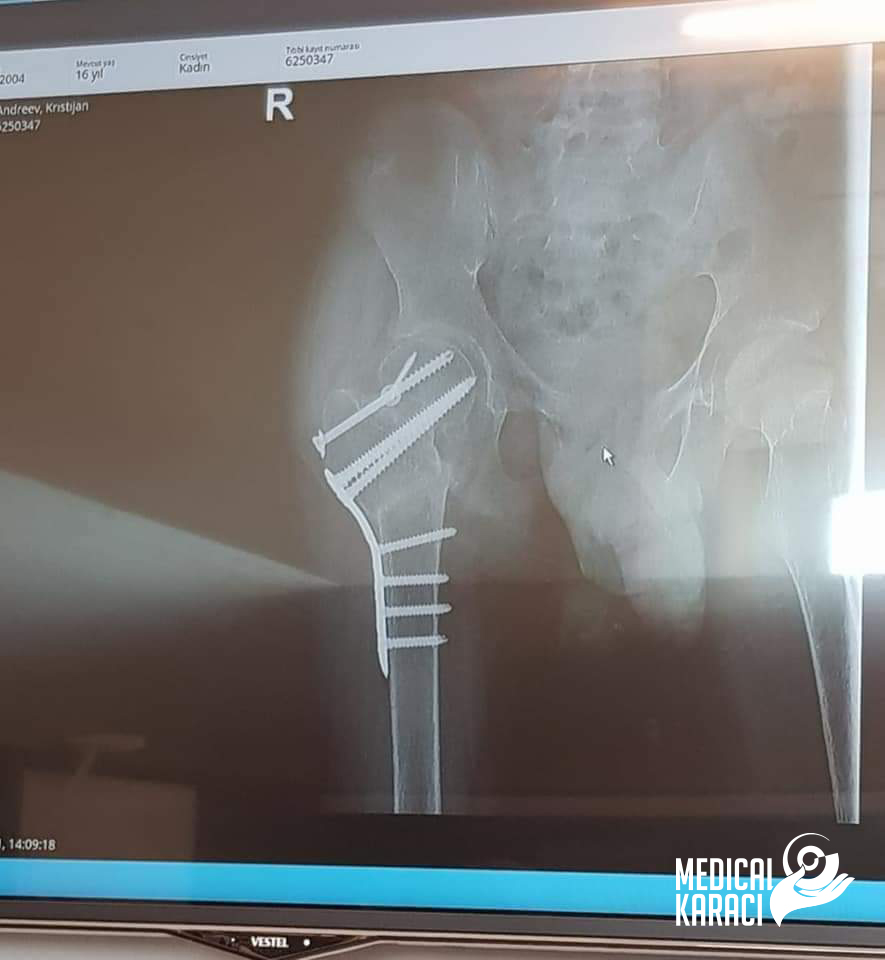

Kristijan e dete na 17 godishna vozrast koj boleduva od mnogu teshka forma na Autizam i Epilepsija, vo Dekemvri 2020 padna i go skrshi kolkot. Koga site vo Makedonija ni kazuvaa deka nemoze da go operiraat i deka nema nikogash veke da zastane na noze i da odi jas ne se otkazav, no nitu ti mila moja Zvezdelina Kara i Karaci Tours Medical denonokno istrazuvashe, go barashe i go najde najdobroto za Kristijan !! Kristijan blagodarenie na tebe i na Prof. Dr. Mustafa Kürklü ZASTANA NA NOZE I ODI 🙏🙏Neznam kako da ti se zablagodaram za se shto napravi i pravish za Kristijan, za celata organizacija vo bolnicata Memorial Bahcelievler Hospital za celo vreme shto beshe i si so nas. Zatoa shto se raduvash i se borish zaedno so nas🙏